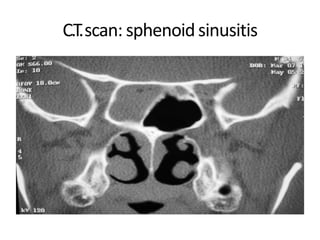

C.T.scan: sphenoidsinusitis

• Most reliableimaging modality for • sinusitis at present • Plain axial, coronal and sagittal cuts of 3 mm • Contrast for suspected vascular, • neoplastic, inflammatory lesions • Helps to delineate the extent of disease, define anatomical variants and study the relationship of sinuses with • surrounding structures • Indications: • Recurrent acute/chronic sinusitis not responding to medical treatment • Before endoscopic sinus surgery • Impending complications of sinusitis C.T.scan ofNose andPNS